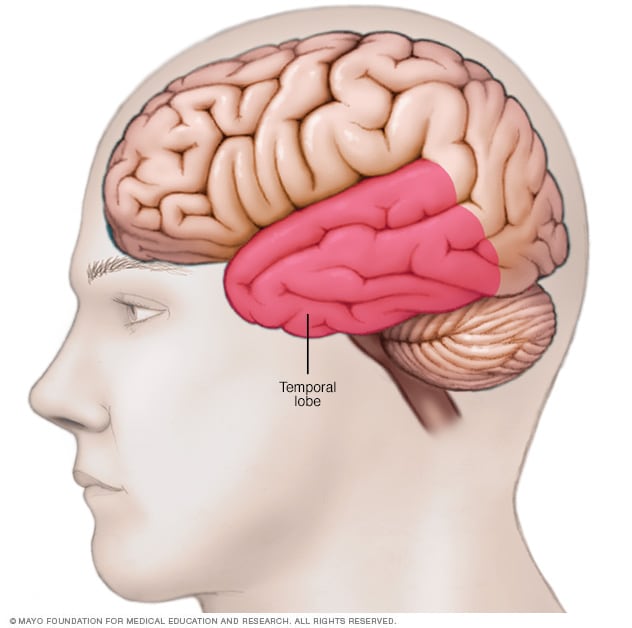

What Is Temporal Lobe

What Is Temporal Lobe

Temporal Lobe Anatomy Location Function Damage Epilepsy

Location Of Temporal Lobe Mayo Clinic

Temporal Lobe SpinalCord

Temporal Lobe SpinalCord

Temporal Lobe The Definitive Guide Biology Dictionary

Temporal Lobe Function Location And Structure

Temporal Lobe

Temporal Lobe What Is It Location Structure Functions Injuries

Temporal Lobe What Is It Location Structure Functions Injuries